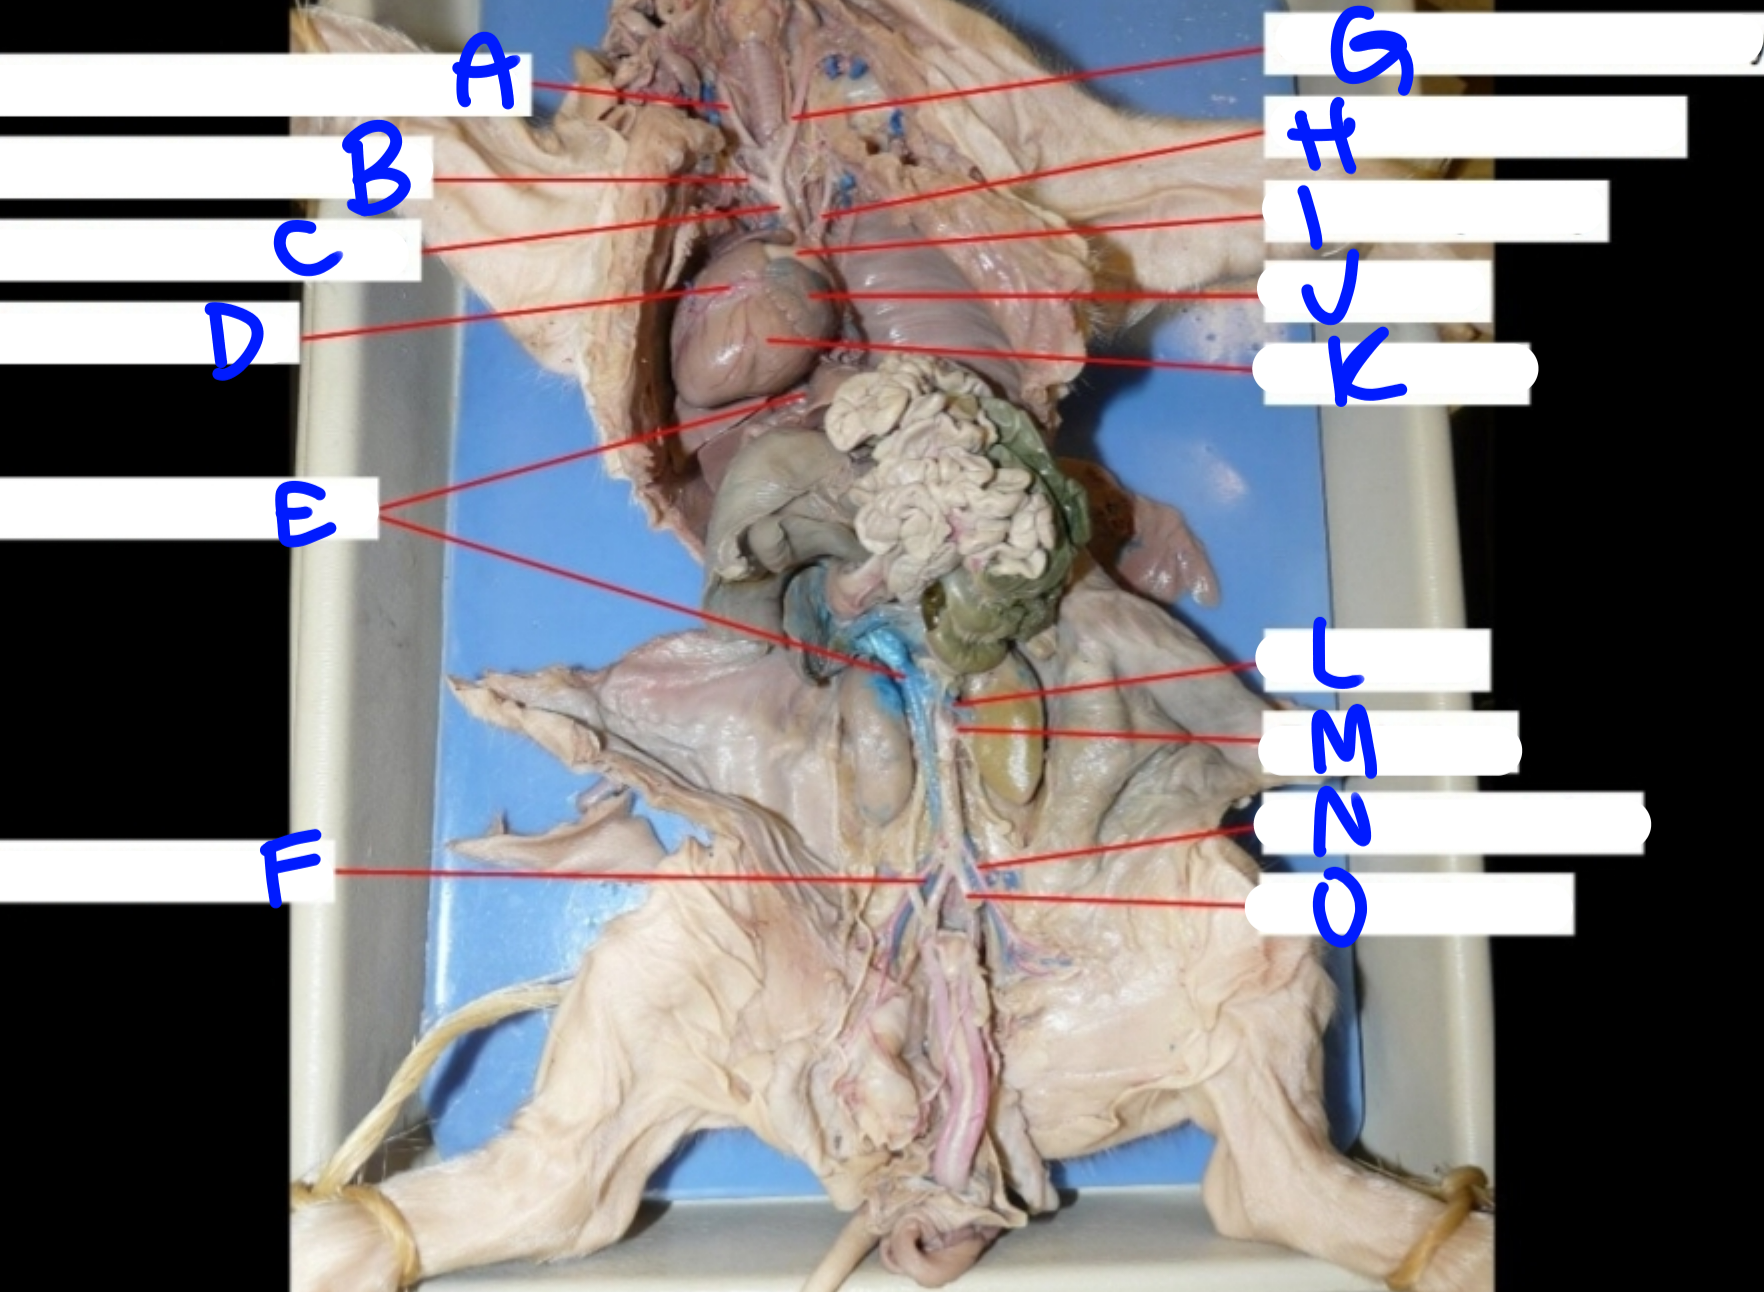

A

Right common carotid artery - delivers oxygenated blood to the head & neck

B

Right subclavian artery - delivers oxygenated blood to the upper body

C

Brachiocephalic artery - delivers oxygenated blood to the upper body

D

Coronary artery - delivers oxygenated blood to the heart

E

Posterior vena cava - carries deoxygenated blood from the lower body to the right side of the heart

G

Left common carotid artery - delivers oxygenated blood to the upper body

H

Left subclavian artery - carries oxygenated blood to the upper body

I

Pulmonary artery - delivers deoxygenated blood from the heart to the lungs

J

Left atrium - delivers oxygenated blood to the left ventricle

K

Left ventricle - delivers oxygenated blood to the systemic circuit

L

Renal vein - delivers blood from the kidney & ureter to the inferior vena cava

M

Renal artery - delivers blood from the kidney & ureter to the inferior vena cava

O

Umbilical artery - carries deoxygenated blood to the placenta